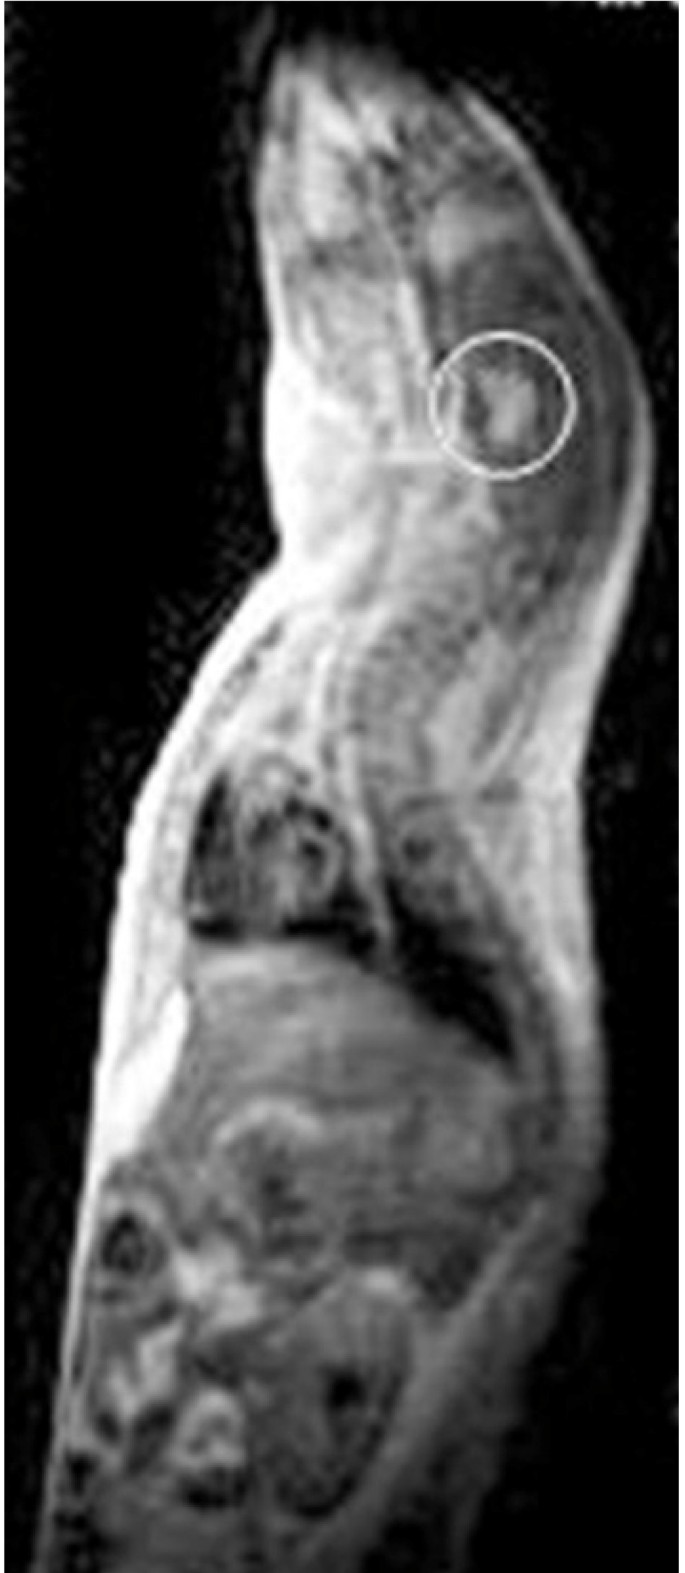

Recently, our group suggested a critical role for high-mobility group A2 (HMGA2) gene in pituitary oncogenesis. In fact, transgenic mice expressing high levels of the HMGA2 gene develop pituitary adenomas secreting prolactin and growth hormone [6], (Figure 1).